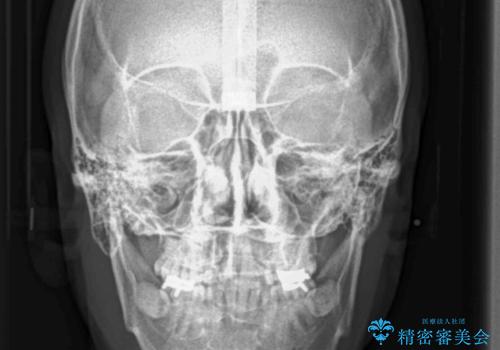

患者様の「できるだけ短期間で治療を終わらせたい、セラミックが入れられたら良いので大がかりなことはしたくない」とのご要望により、3Dシミュレーションを何度も行い患者様とのコンサルを重ね、上顎左右犬歯と左下2を抜歯して②のプランである補綴前矯正(インビザライン)を行うことにしました。

小臼歯の歯根長が長いことを治療前にレントゲンで確認し抜歯部位を決定しました。